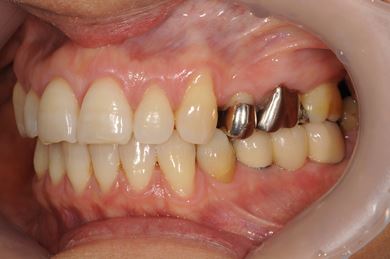

インプラントの症例写真 IMPLANT

抜歯即日スピードインプラント治療

| 性別/年齢 | 女性 / 37歳 | ||||||||||||||||||||||||||||||||

| 主訴 | ブリッジの支えとなっている歯が虫歯になり、ブリッジが難しくなったため、インプラントか義歯かの相談で来院。 | ||||||||||||||||||||||||||||||||

| 治療方針 | 抜歯と同時にインプラント治療を行い、治療期間を短縮する。 | ||||||||||||||||||||||||||||||||

| 治療内容 | インプラント4本(抜歯即日スピードインプラント治療)、ハイブリッドセラミッククラウン6本 | ||||||||||||||||||||||||||||||||

| 総治療費 | 1,236,165円 | ||||||||||||||||||||||||||||||||

| 治療期間 | 1年5ヶ月 |